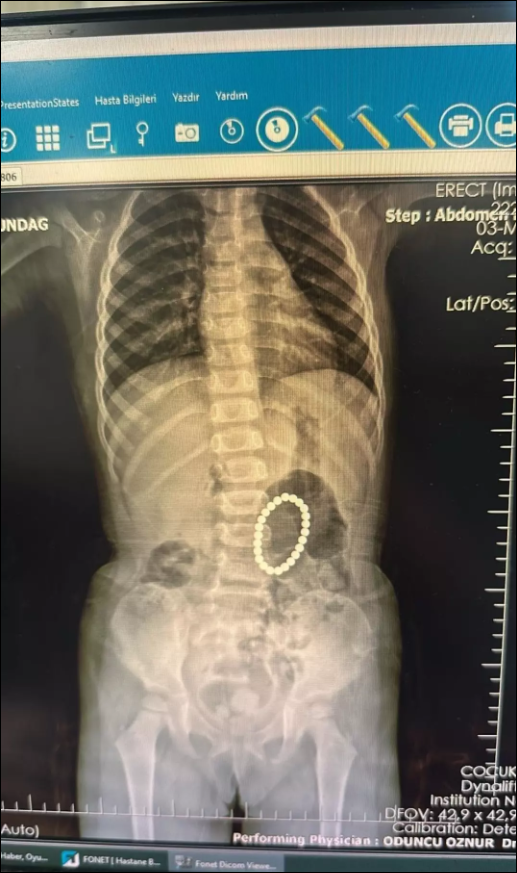

küçük kızın bağırsağından çıkanlar şaşkına çevirdi.

İlk defa böyle bir vaka ile denk geldiklerini belirten Doktor Selim Özkaya, yapılan ameliyatın ardından başarılı bir şekilde tamamlandığını söyledi. Mıknatısların bağırsaklarda kısmen delinmelere neden olduğunu belirten Dr. Özkaya, “Hastamız 4 yaşında kız hasta. Yoğun karın ağrısı nedeniyle Şırnak’ta devlet hastanemize başvurmuş, yapılan tetkiklerinde yabancı cisim yuttuğu tespit edilmiş. Bunun üzerine endoskopi yapılmak üzere hastanemize Gastroentoloji bölümüne sevk edildi.